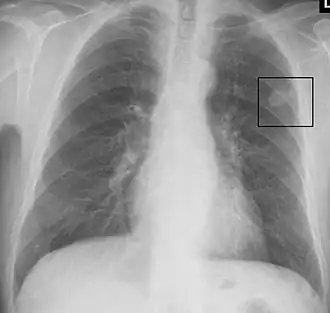

- Рак лёгкого

- Рак щитовидной железы